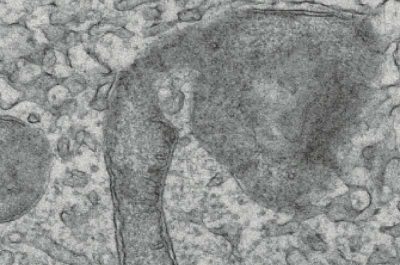

Meningiomi- immagine: (In alto) Immagine di microscopia elettronica a trasmissione dei mitocondri del meningioma dopo il trattamento con l’agonista STING 8803, che indica il collasso delle strutture mitocondriali interne e la compromissione della doppia membrana. (In basso) Immagine di microscopia elettronica a scansione delle cellule di meningioma trattate con 8803 che mostra una membrana plasmatica con pori irregolari compatibili con piroptosi. Crediti: Mark Youngblood, MD, Ph.D.

Infine, per identificare i meccanismi cellulari che promuovono la citotossicità nelle cellule tumorali del meningioma, gli scienziati hanno utilizzato il sequenziamento dell’RNA e la microscopia elettronica per studiare le cellule tumorali del meningioma che erano state trattate con l’agonista STING.

Inaspettatamente, hanno scoperto che il farmaco innesca percorsi di necrosi programmata e attiva la proteina Gasdermin D, che a sua volta crea “pori” nella membrana cellulare tumorale. Di conseguenza, la mancanza di integrità della membrana innesca una forma improvvisa e incontrollata di morte cellulare che rilascia antigeni nel microambiente tumorale, causando una risposta infiammatoria.